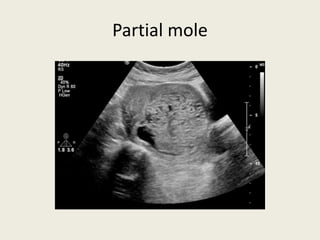

Molar pregnancy

• The ultrasound is a classic example of a SNOW STORM appearance with in the

uterine cavity

MOLAR PREGNANCY:

• A type of benign gestational trophoblastic pregnancy often called “hydatidiform mole”

• 2 types: complete mole (no fetal parts) vs partial mole (partial fetal parts)

• Common presentation of Complete Molar Pregnancy:

– Often have excessively higher than expected hCG levels for gestational age

– abnormal painless vaginal bleeding

– Uterine size larger than expected for gestational age

• Ultrasound findings with in uterine cavity:

– Complete mole: pathognamonic “snow storm” appearance with absence of fetal heart beat or fetal

parts

– Partial mole: presence of abnormal incomplete fetal parts with absence of fetal heart beat

Partial mole

Molar pregnancy • Theultrasound is a classic example of a SNOW STORM appearance with in the uterine cavity =

MOLAR PREGNANCY: • Atype of benign gestational trophoblastic pregnancy often called “hydatidiform mole” • 2 types: complete mole (no fetal parts) vs partial mole (partial fetal parts) • Common presentation of Complete Molar Pregnancy: – Often have excessively higher than expected hCG levels for gestational age – abnormal painless vaginal bleeding – Uterine size larger than expected for gestational age • Ultrasound findings with in uterine cavity: – Complete mole: pathognamonic “snow storm” appearance with absence of fetal heart beat or fetal parts – Partial mole: presence of abnormal incomplete fetal parts with absence of fetal heart beat